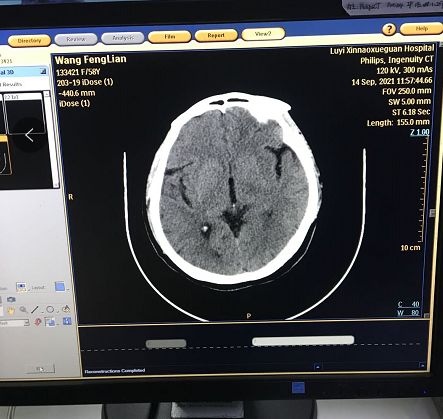

后開機(jī)測試,可以正常進(jìn)入系統(tǒng),做預(yù)熱正常,但是掃描時(shí)出現(xiàn)圖像亂碼

根據(jù)此圖像顯示問題應(yīng)該在NGBP卡上,重新插拔NGBP卡,重新安裝CIRS軟件后依舊,后清理NGBP卡上小內(nèi)存條,清理完成重新安裝后正常